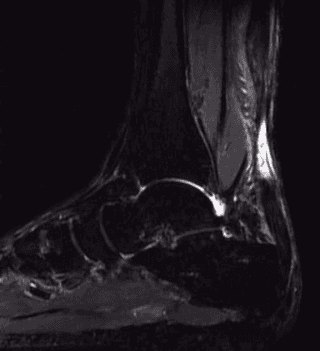

La diagnosi può essere approfondita con esami strumentali, quali l’ecografia e la risonanza magnetica.

Se la diagnosi clinica sembra abbastanza facile, e viene spesso completata dalla risonanza magnetica e dall’ecografia, bisogna ricordare che nel 20% dei casi questa lesione non viene riconosciuta, il che porta ad un aggravamento del quadro clinico, dovuto alla retrazione tendinea, che aumenta progressivamente nei primi 15 giorni seguenti alla lesione.